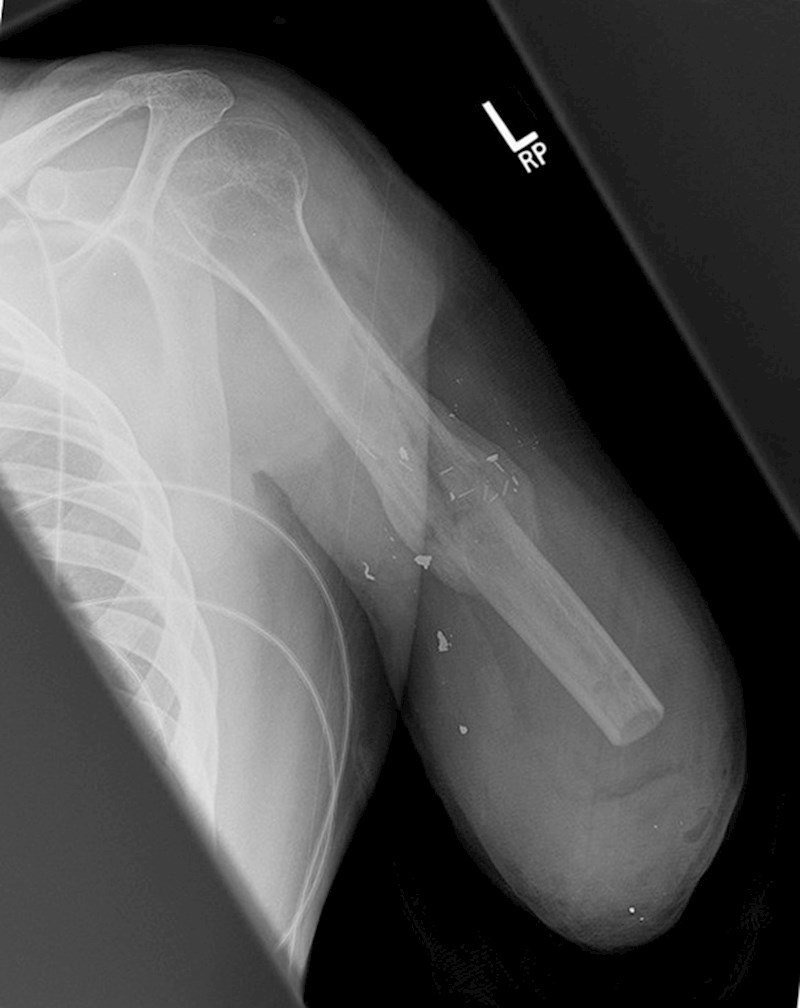

Ovako izgleda rendgenska slika osobe s amputiranom rukom.